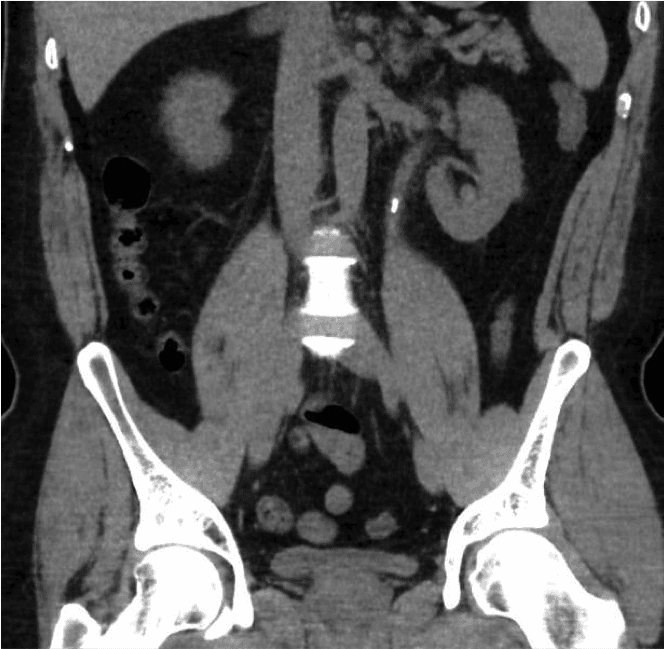

腎結石是現代最常見的疾病之一。其發生率在不同地區差異大,西方國家的男性發生率為8%至19%,女性為3%至5% [1,2]。 2000年至2010年,英國因腎結石入院治療的人數增加了63%,達到83,050人次 [3]。腎結石盛行率的不斷上升給我們的醫療保健系統帶來了沉重的經濟和臨床負擔。腎結石可能在因其他原因進行的掃描中偶然出現,或出現疼痛、泌尿道感染或血尿(尿液中帶血)等症狀。